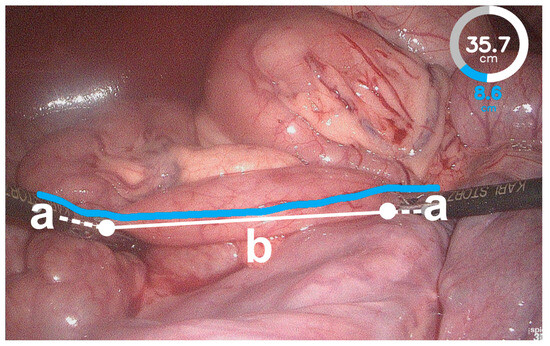

- Wagner, M.; Mayer, B.F.B.; Bodenstedt, S.; Stemmer, K.; Fereydooni, A.; Speidel, S.; Dillmann, R.; Nickel, F.; Fischer, L.; Kenngott, H.G. Computer-Assisted 3D Bowel Length Measurement for Quantitative Laparoscopy. Surg. Endosc. 2018, 32, 4052–4061. [Google Scholar] [CrossRef]

- Wagner, M.; Mayer, B.F.B.; Bodenstedt, S.; Kowalewski, K.F.; Nickel, F.; Speidel, S.; Kenngott, H.G.; Müller-Stich, B.P. Comparison of Conventional Methods for Bowel Length Measurement in Laparoscopic Surgery to a Novel Computer-Assisted 3D Measurement System. Obes. Surg. 2021, 31, 4692–4700. [Google Scholar] [CrossRef]